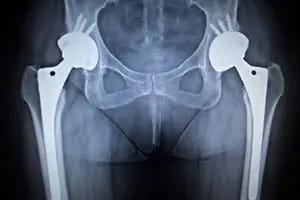

Hip Replacement Surgery